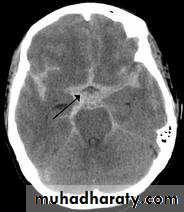

Non contrast high resolution CT scan which can demonstrate the amount of blood in the cisterns and fissure, ventricular size, associated intracranial hemorrhage, infarction and predict the location of aneurysm.

Hydrocephalus ( usually obstructive by blood clot or communicating type which develop often late due to toxic effect of blood breakdown)

Cerebral vasospasm